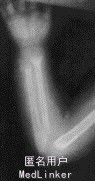

头围43cm,前囟2.5X2.5cm,枕秃,方颅,未出牙,胸廓无畸形,无赫氏沟,无手足镯征。 电解质:钙1.96mmol/L,磷 1.0mmol/L。X线示:腕骨骨化中心1枚,尺桡远端呈毛刷样改变,干骺端皮质疏松,临时钙化带消失。

诊断为:维生素D缺乏性佝偻病(激期) 入院后予维生素D3000IU/d口服,钙剂300mg/d口服。1周后出院,嘱按时服用维生素D及钙剂,增加户外活动时间,定期复查。